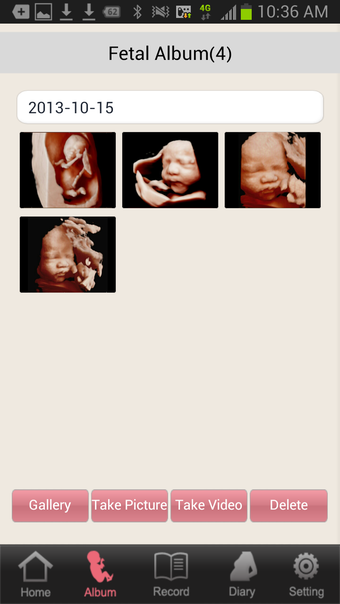

1) Browse Sonogram on a mobile device

- You can view ultrasound images you have received from a Samsung Medison ultrasound system on your device.

- You can also view an image of your baby or a part of your baby's body (if it was saved to your device) from your ultrasound system at your hospital